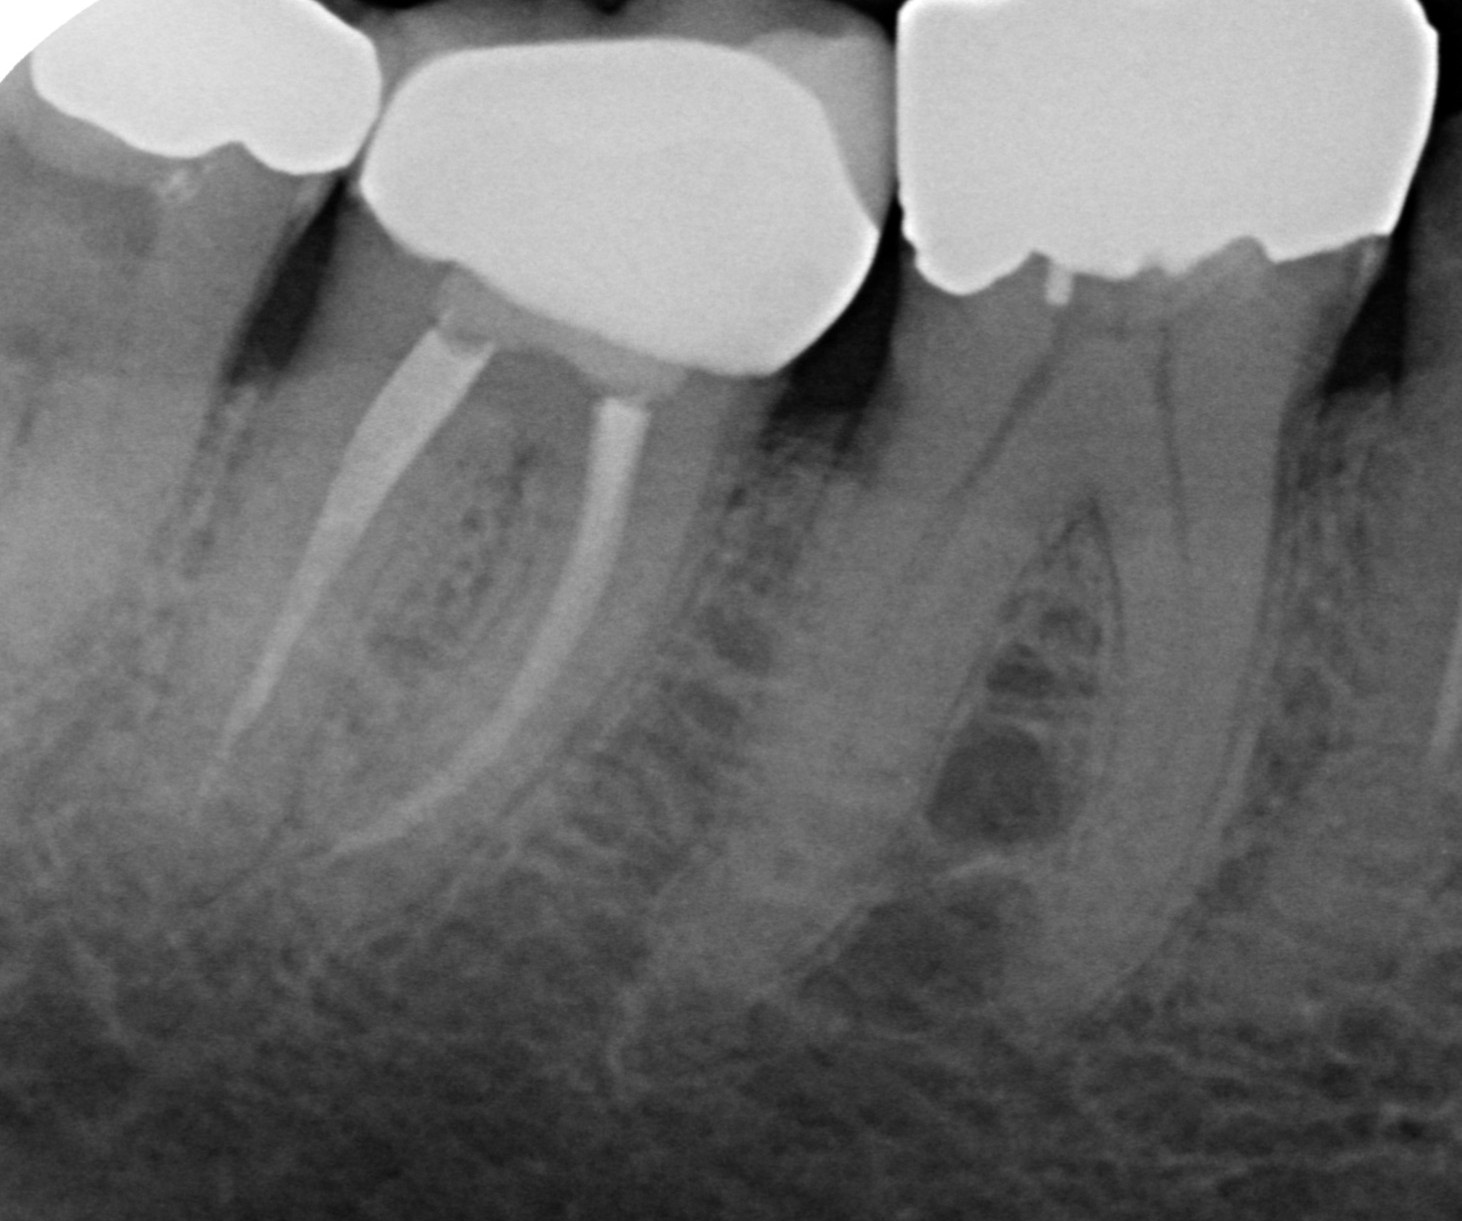

Root Canal Therapy

Root canal therapy helps save a tooth that is badly damaged or severely infected. Successful treatment eliminates the infection and the resulting pain, thereby preventing tooth loss.

Root canal therapy focuses on removing all infected or inflamed tissue from the centre of the tooth. Thus, eliminating the infection and resultant pain.